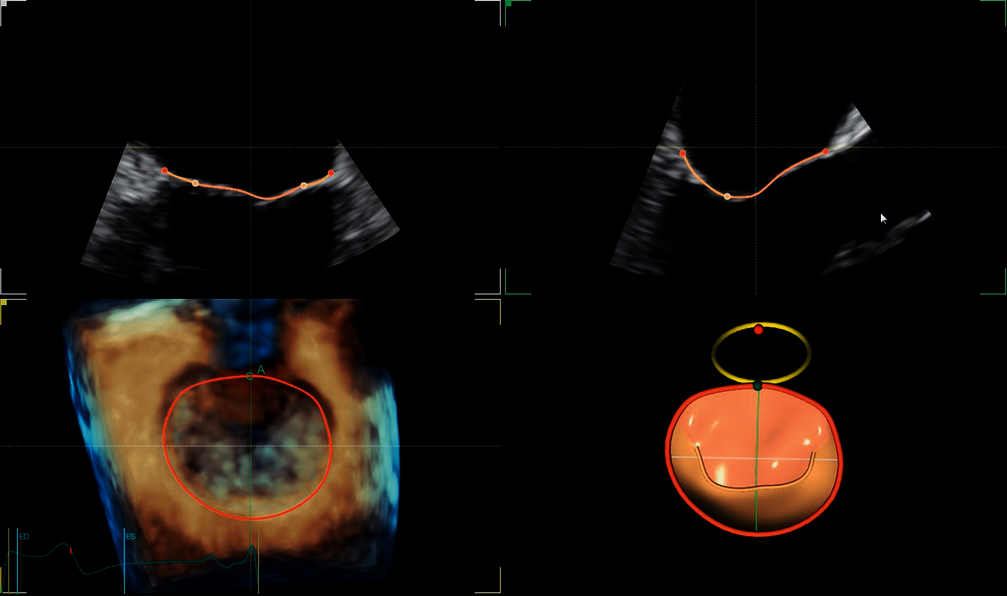

4D AUTO LVQ: Fully integrated tool for visualisation and reproducible quantification of the left ventricle from 4D volume datasets.

4D AUTO MVQ: This fully integrated analysis tool supports you in TEE/TTE examinations as well as the visualisation and quantification of mitral valve structures and the mitral valve annulus.

4D AUTO AVQ: This fully integrated tool automatically segments and quantifies the aortic outflow tract and helps, among other things, to select the right valve prosthesis for TAVI/TAVR procedures.